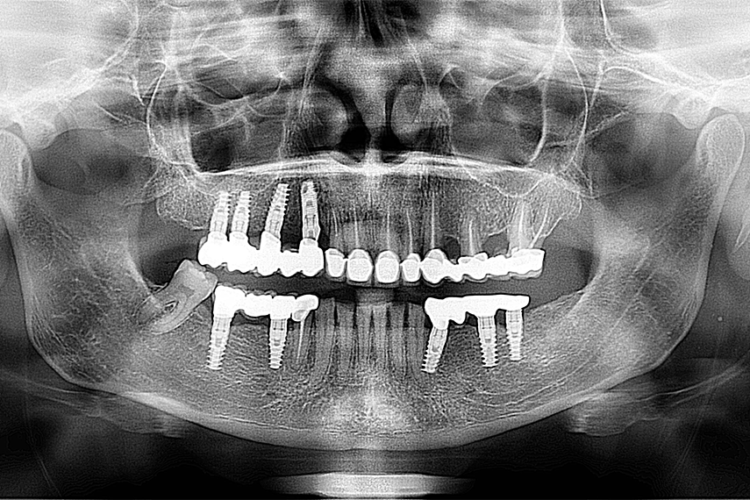

Caz reabilitare orala complexa pe implanturi si dintii restanti cu fatete si coroane dentare din ceramica hibrida

Pacienta in varsta de 43 de ani s-a prezentat in clinica pentru reabilitare orala totala. Aceasta a cuprins inserare de  implanturi si restaurari protetice ceramice hibride si fatetari hibride pe dintii restanti, cu rezultate estetice deosebite si restabilirarea functionalitatii masticatorii.